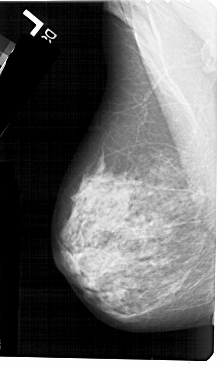

A_1322_1.LEFT_MLO

LEFT_MLO LINES 5491 PIXELS_PER_LINE 3271 BITS_PER_PIXEL 12 RESOLUTION 43.5 NON_OVERLAY